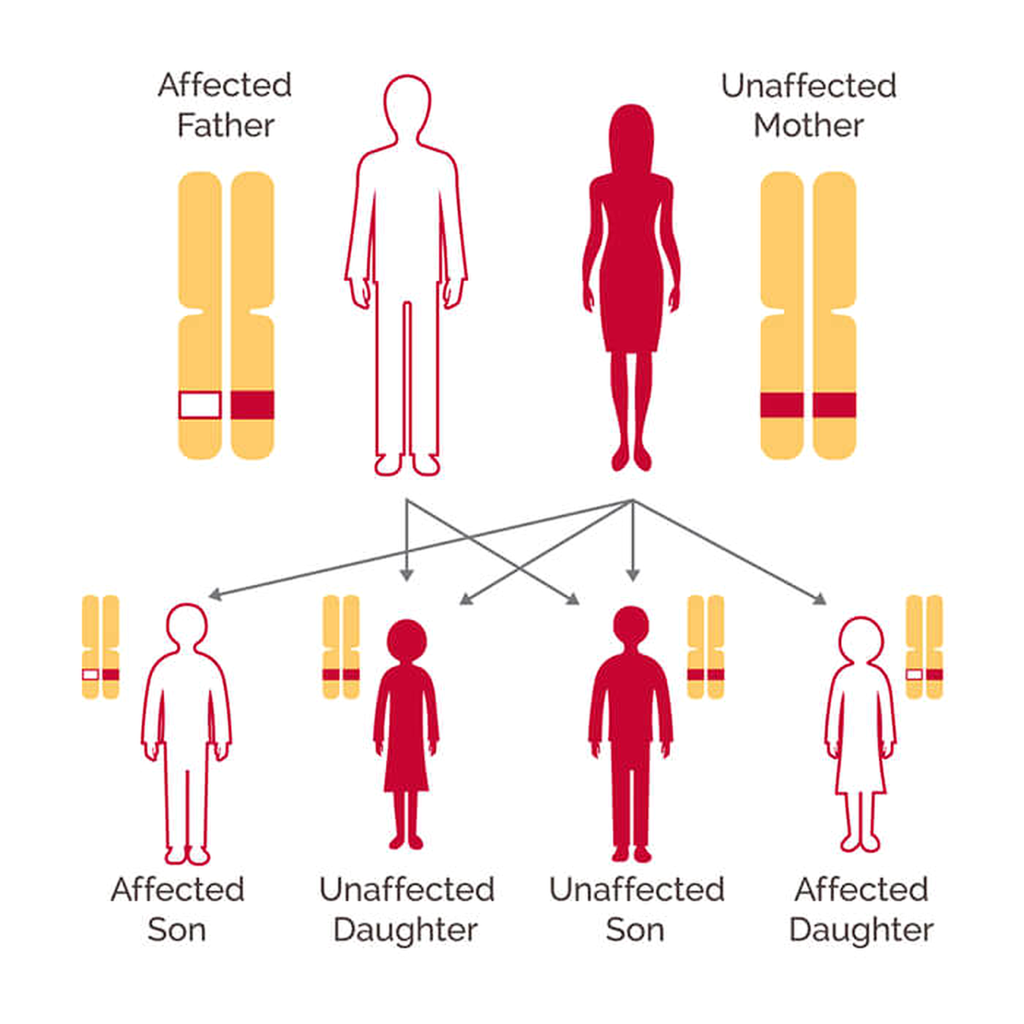

- Family history of breast cancer